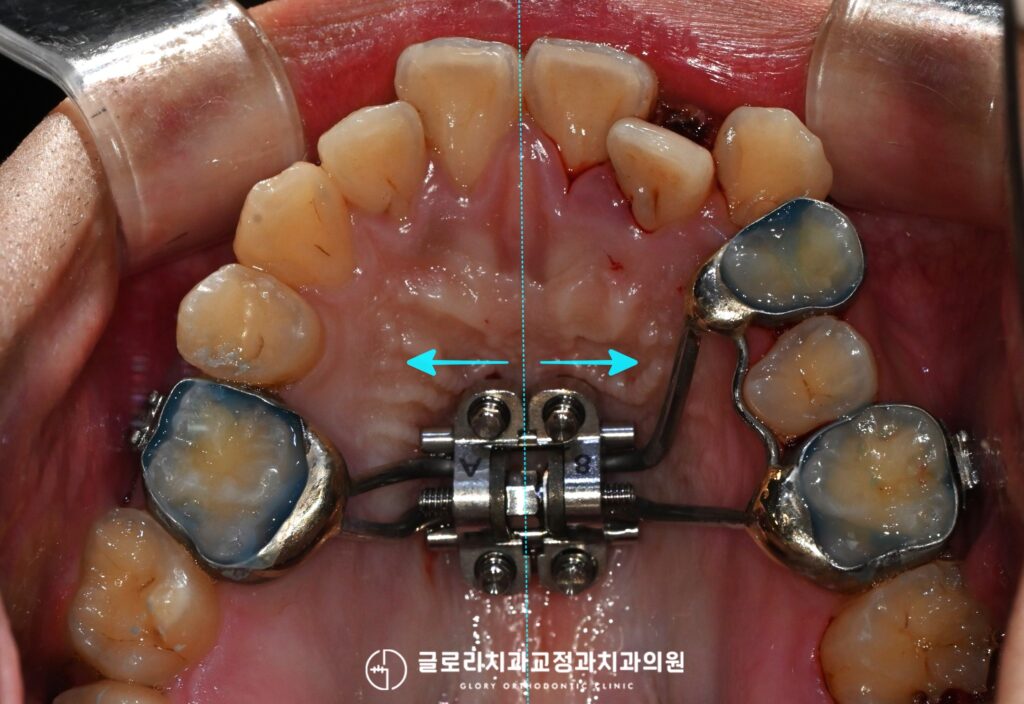

안녕하세요, 망우동 교정치과 김정은 원장입니다:) 어금니는 Class I, 치성 1급 형태로 잘 물리지만유독 앞니 부분만 공간이 떠 있는 상태인 분들이…